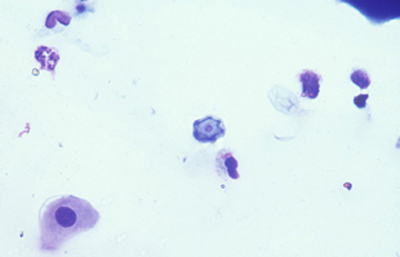

Las coloraciones empleadas en extendidos corneales para visualizar los quistes y trofozoitos de Acanthamoebas usando métodos sencillos son múltiples, siendo las que nos parecen más recomendables las coloraciones de Giemsa y el Acido Periódico de Schiff (PAS), (Figura 33 y 34) ambas usuales en los laboratorios de patología.

Fig. 33 PAS, Original x250

Fig. 34 PAS, Original x160

El examen de las perparaciones sin colorear en campo claro y bajo Contraste de Fases también permite una buena visualización de las formas quísticas de Acanthamoeba. (Figura 35)

Fig. 34 Contraste de fase. Original x160

Fig. 34 Grocott. Original x250

En nuestra práctica empleamos usualmente el Contraste de Fases, el Blanco de Calcofluor, la coloración de Giemsa, y frecuentemente la de PAS. Las tres primeras son más sencillas y rápidas y pueden practicarse en un mismo extendido. Estas técnicas y coloraciones son las mismas que empleamos para el estudio de extendidos en queratitis micóticas.